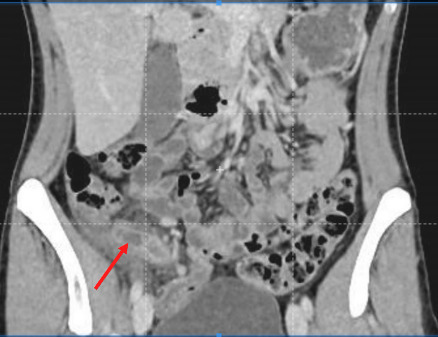

Avant l’ère des explorations radiologiques, la triade fièvre-défense en fosse iliaque droite-hyperleucocytose poussait à l’indication chirurgicale, avec un taux non négligeable (jusqu’à 25 %) d’appendicectomies effectuées sur un appendice sain. La réalisation systématique d’une imagerie abdominale a permis de diminuer significativement le taux d’appendicectomies inutiles. Les recommandations émises par les Sociétés françaises de chirurgie digestive et de radiologie préconisent donc la réalisation systématique d’une imagerie lors de la suspicion clinico-biologique d’appendicite aiguë (fig. 1).

Scanner abdominopelvien injecté : la référence

Le scanner abdominopelvien avec injection intraveineuse de produit de contraste est l’examen de référence, avec une excellente performance diagnostique. Il permet, dans le même temps, d’éliminer de nombreux diag­nostics différentiels et détermine la présence ou non d’une complication de l’appendicite, telle qu’un abcès ou une péritonite. Le diagnostic ­positif repose sur une augmentation du diamètre de l’appendice, une infiltration de la graisse périappendiculaire, un épaississement et une prise de contraste de ses parois (fig. 2).